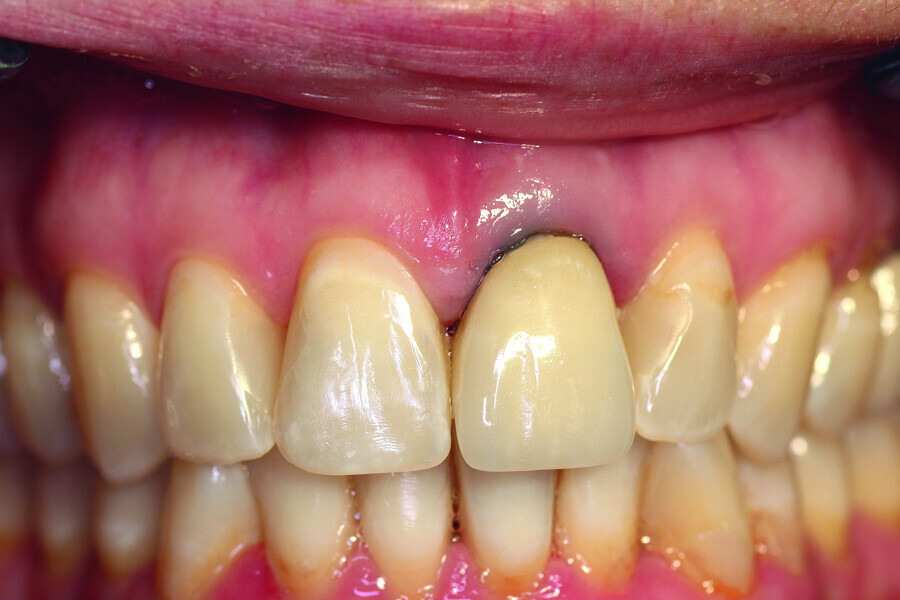

Fig. 1: Initial clinical situation.